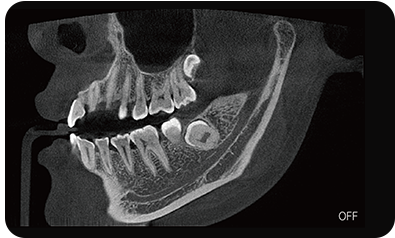

超能去伪 至臻影像

临床样片